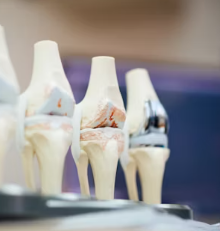

질병이 오래 지속되고 염증이 심하면 관절 연골과 뼈가 손상되어 관절 모양이 변형될 수 있습니다. 손가락 관절이 붓고 휘어지거나, 손목 관절이 변형되어 움직임이 제한될 수 있습니다.

관절 변형은 류마티스 관절염이 어느 정도 진행되었음을 의미하며, 한번 발생하면 되돌리기 어렵습니다. 조기에 진단받고 치료하는 것이 관절 변형을 막는 데 중요합니다.